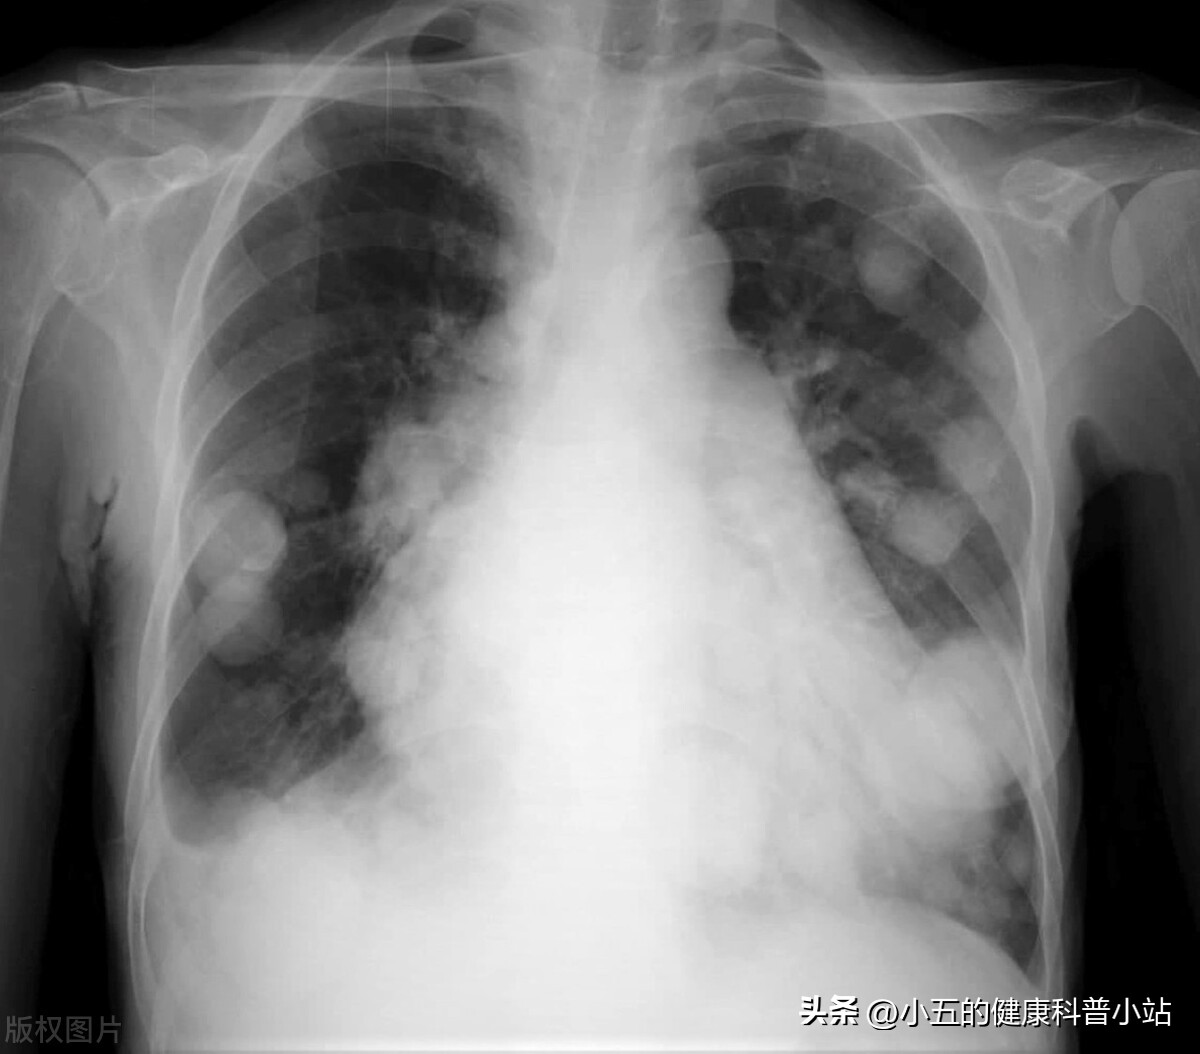

1个月前张大爷又开始出现剧烈的咳嗽,伴咳白粘痰,并且又轻度的呼吸不畅,他以为是慢性支气管炎又犯了,于是还是老样子来到医院就诊。 医院给他完善了肺部CT后发现张大爷的肺部有片状的毛玻璃样阴影,结合的血液检查和核酸检查的结果最终诊断为病毒性肺部,合并慢性支气管哮喘急性期 ,于是急忙将其收治医院。经过一段时间的住院治疗后,张大爷的症状有了明显好转, 但就是指脉氧上不去,脱氧状态下只有95%-96%左右,并且还是有少量咳痰,于是医生建议张大爷回家后继续口服一段时间药物,其中就有盐酸氨溴索片 ,医生嘱咐张大爷规范用药,一个月后再复查肺部CT。